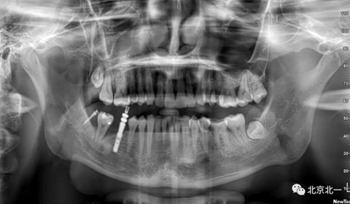

患者、男、40歲,下頜牙缺失數(shù)年來院咨詢種植。

檢查:46缺失, 47傾斜, 1度松動(dòng), 未見48萌出,

CBCT:骨量高度及寬度可, 48埋伏,低位阻生.37近中骨吸收

診斷:下頜牙列缺損, 48低位埋伏阻生 37 牙周炎

治療計(jì)劃:46種植, 同期拔除48 正畸扶正47.

術(shù)后拍片。